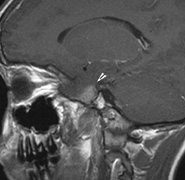

Intracranial leptomeningeal capillary vascular malformation (Figs. 21 and 22) is associated with seizures and contralateral neuromuscular weakness. Central nervous system involvement correlates highly with ipsilateral involvement of the V1 dermatome by a PWS.208,218

Fig. 22. Axial T2-weighted (a) and coronal T1-weighted (b) images of a 16-year-old boy with a port-wine lesion over the right side of his face. The right hemisphere is markedly atrophic and abnormal draining veins are seen within the right lateral ventricle (arrowheads). (c, d) The entire right hemisphere is covered by an enhancing pial angioma and the choroid plexi are enlarged. Enhancing retinal angiomas (arrows), typical of Sturge-Weber syndrome, are seen in (d).